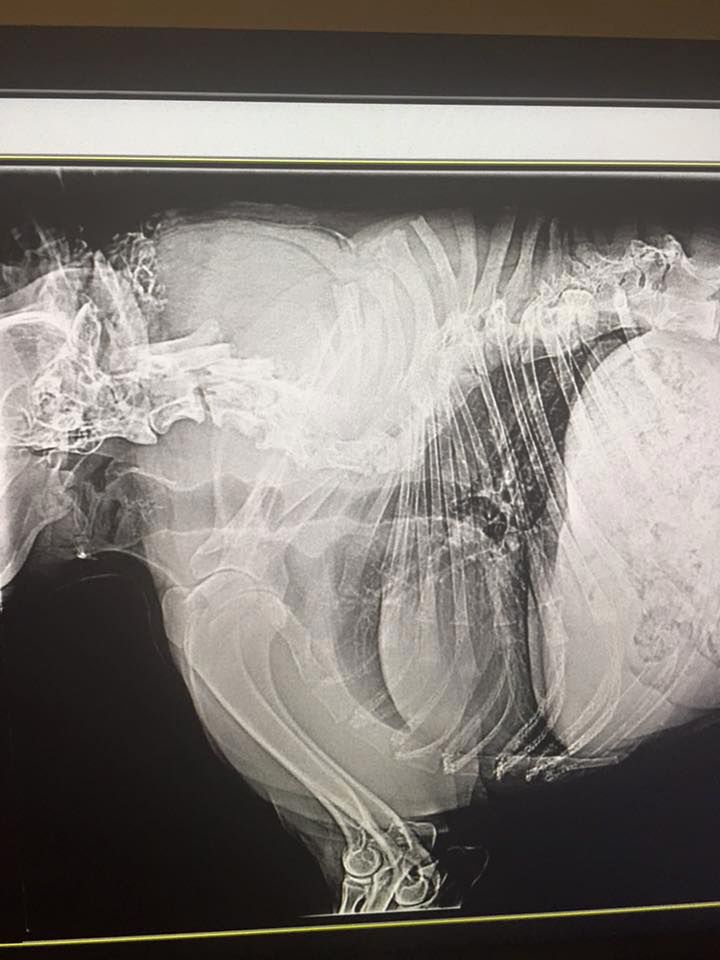

/ 6Czarno na białym

Jego kręgi miejscami są zrośnięte, stąd widoczny efekt braku szyi.